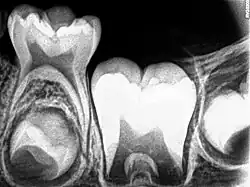

Although tooth eruption occurs at different times for different people, a general eruption timeline exists. Typically, humans have 20 primary (baby) teeth and 32 permanent teeth.[44] Tooth eruption has three stages. The first, known as deciduous dentition stage, occurs when only primary teeth are visible. Once the first permanent tooth erupts into the mouth, the teeth are in the mixed (or transitional) dentition. After the last primary tooth falls out of the mouth—a process known as exfoliation—the teeth are in the permanent dentition.

Primary dentition starts on the arrival of the mandibular central incisors, usually at eight months, and lasts until the first permanent molars appear in the mouth, usually at six years.[45] The primary teeth typically erupt in the following order: (1) central incisor, (2) lateral incisor, (3) first molar, (4) canine, and (5) second molar.[46] As a general rule, four teeth erupt for every six months of life, mandibular teeth erupt before maxillary teeth, and teeth erupt sooner in females than males.[47] During primary dentition, the tooth buds of permanent teeth develop below the primary teeth, close to the palate or tongue.

Mixed dentition starts when the first permanent molar appears in the mouth, usually at six years, and lasts until the last primary tooth is lost, usually at eleven or twelve years.[48] Permanent teeth in the maxilla erupt in a different order from permanent teeth on the mandible. Maxillary teeth erupt in the following order: (1) first molar (2) central incisor, (3) lateral incisor, (4) first premolar, (5) second premolar, (6) canine, (7) second molar, and (8) third molar. Mandibular teeth erupt in the following order: (1) first molar (2) central incisor, (3) lateral incisor, (4) canine, (5) first premolar, (6) second premolar, (7) second molar, and (8) third molar. Since there are no premolars in the primary dentition, the primary molars are replaced by permanent premolars.[49] If any primary teeth are lost before permanent teeth are ready to replace them, some posterior teeth may drift forward and cause space to be lost in the mouth.[50] This may cause crowding and/or misplacement once the permanent teeth erupt, which is usually referred to as malocclusion. Orthodontics may be required in such circumstances for an individual to achieve a straight set of teeth.